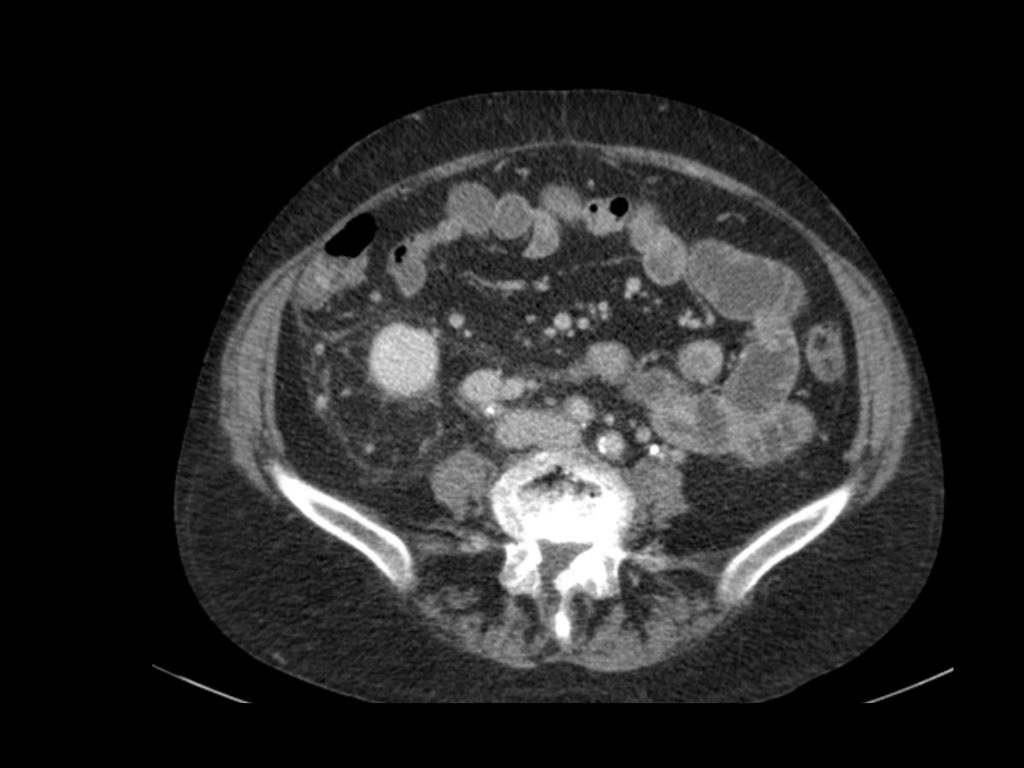

Tổn thương xâm lấn ở cực dưới thận phải, phát triển đáng kể sau sáu tháng, kèm theo hạch bạch huyết lan rộng. Đây được xác định là di căn của ung thư phổi.

Di căn thận thường có kích thước nhỏ, đa ổ và hai bên, với hình thái phát triển xâm lấn.

Các tổn thương này ngấm thuốc nhẹ, kém hơn nhiều so với nhu mô thận bình thường.

Hình ảnh cho thấy bệnh nhân có nhiều tổn thương di căn thận.

Lưu ý huyết khối khối u trong tĩnh mạch thận trái.

Đây là hình ảnh của một bệnh nhân ung thư phổi.

Có một tổn thương di căn ở thận trái và nhiều tổn thương di căn hạch bạch huyết (mũi tên).

Nếu đây là biểu hiện duy nhất, sẽ rất khó để phân biệt với ung thư biểu mô tế bào thận có di căn hạch bạch huyết.